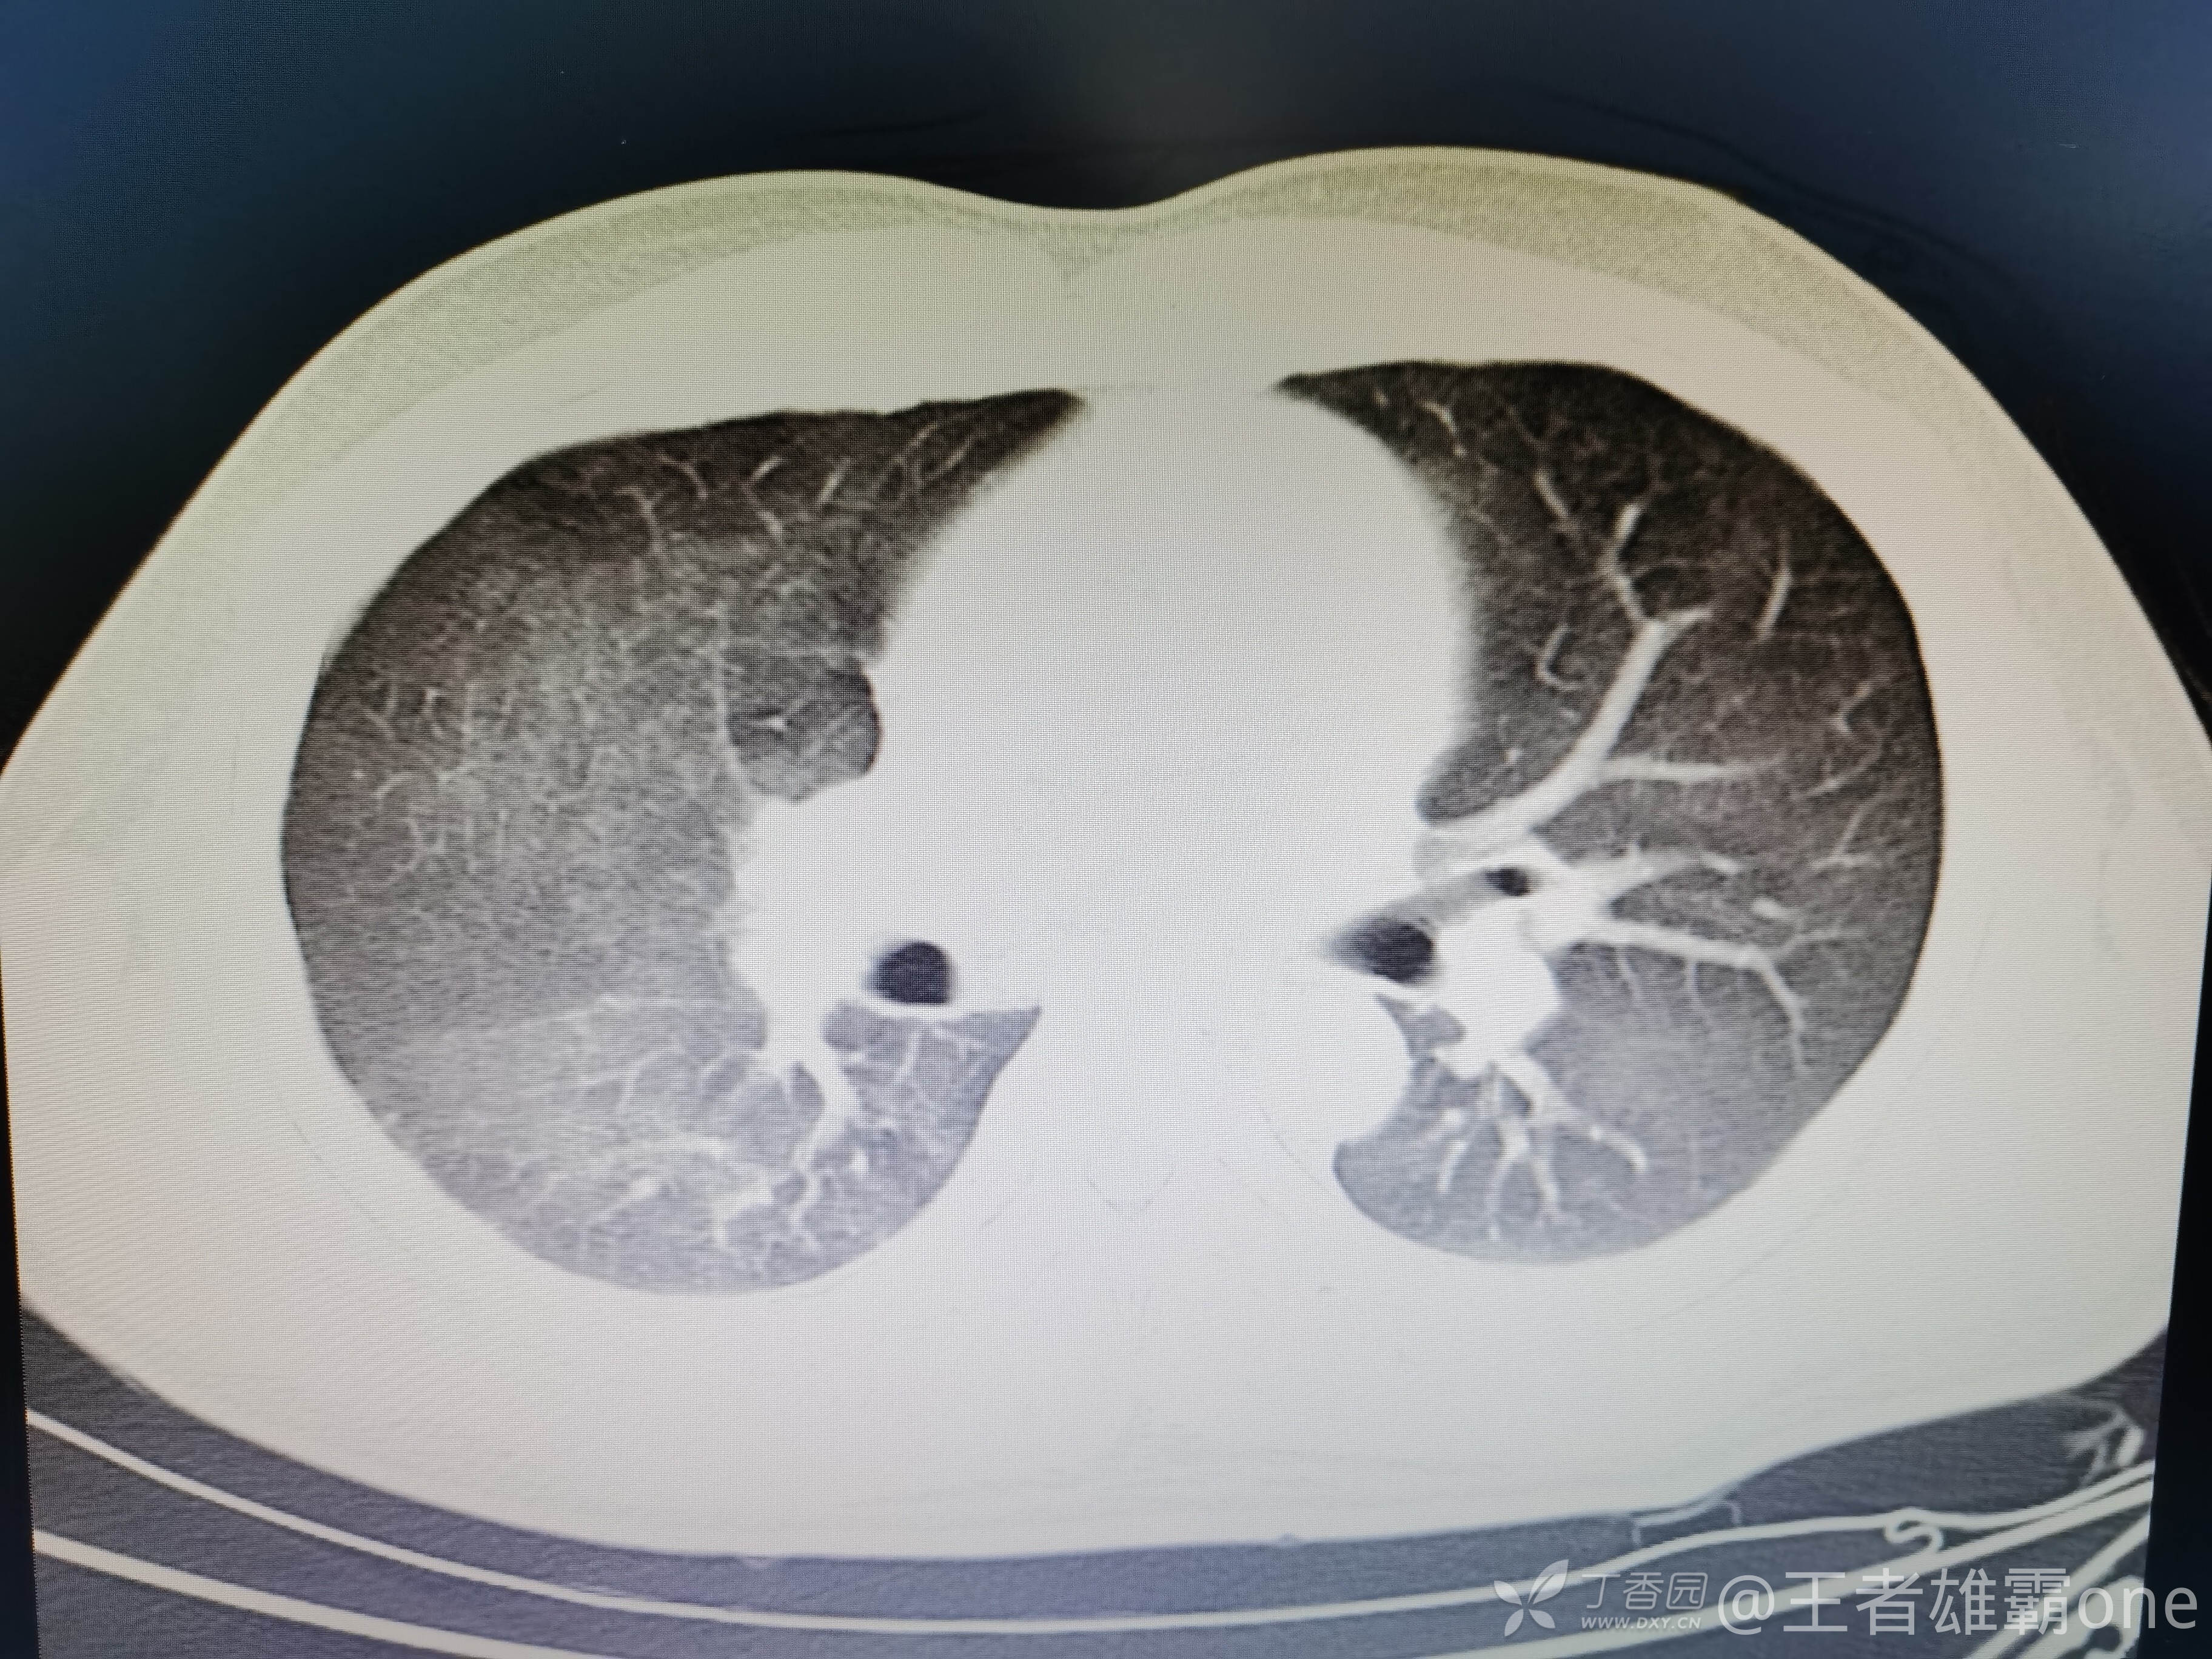

西门开心 推荐男,33岁,否认既往有心脏基础疾病,6-1受伤后急诊行右胫腓骨骨折固定术(术前胸部CT无明显异常,见后面视频前半部分),术后逐渐出现刺激性咳嗽、胸闷,无精神症状,无皮疹,无胸痛,无咯血等。6-6完善胸部CT、脑钠肽前体、心超等辅查,其中脑钠肽前体、心超无明显异常。复查的胸部CT见视频后半部分:

附几张CT图片: